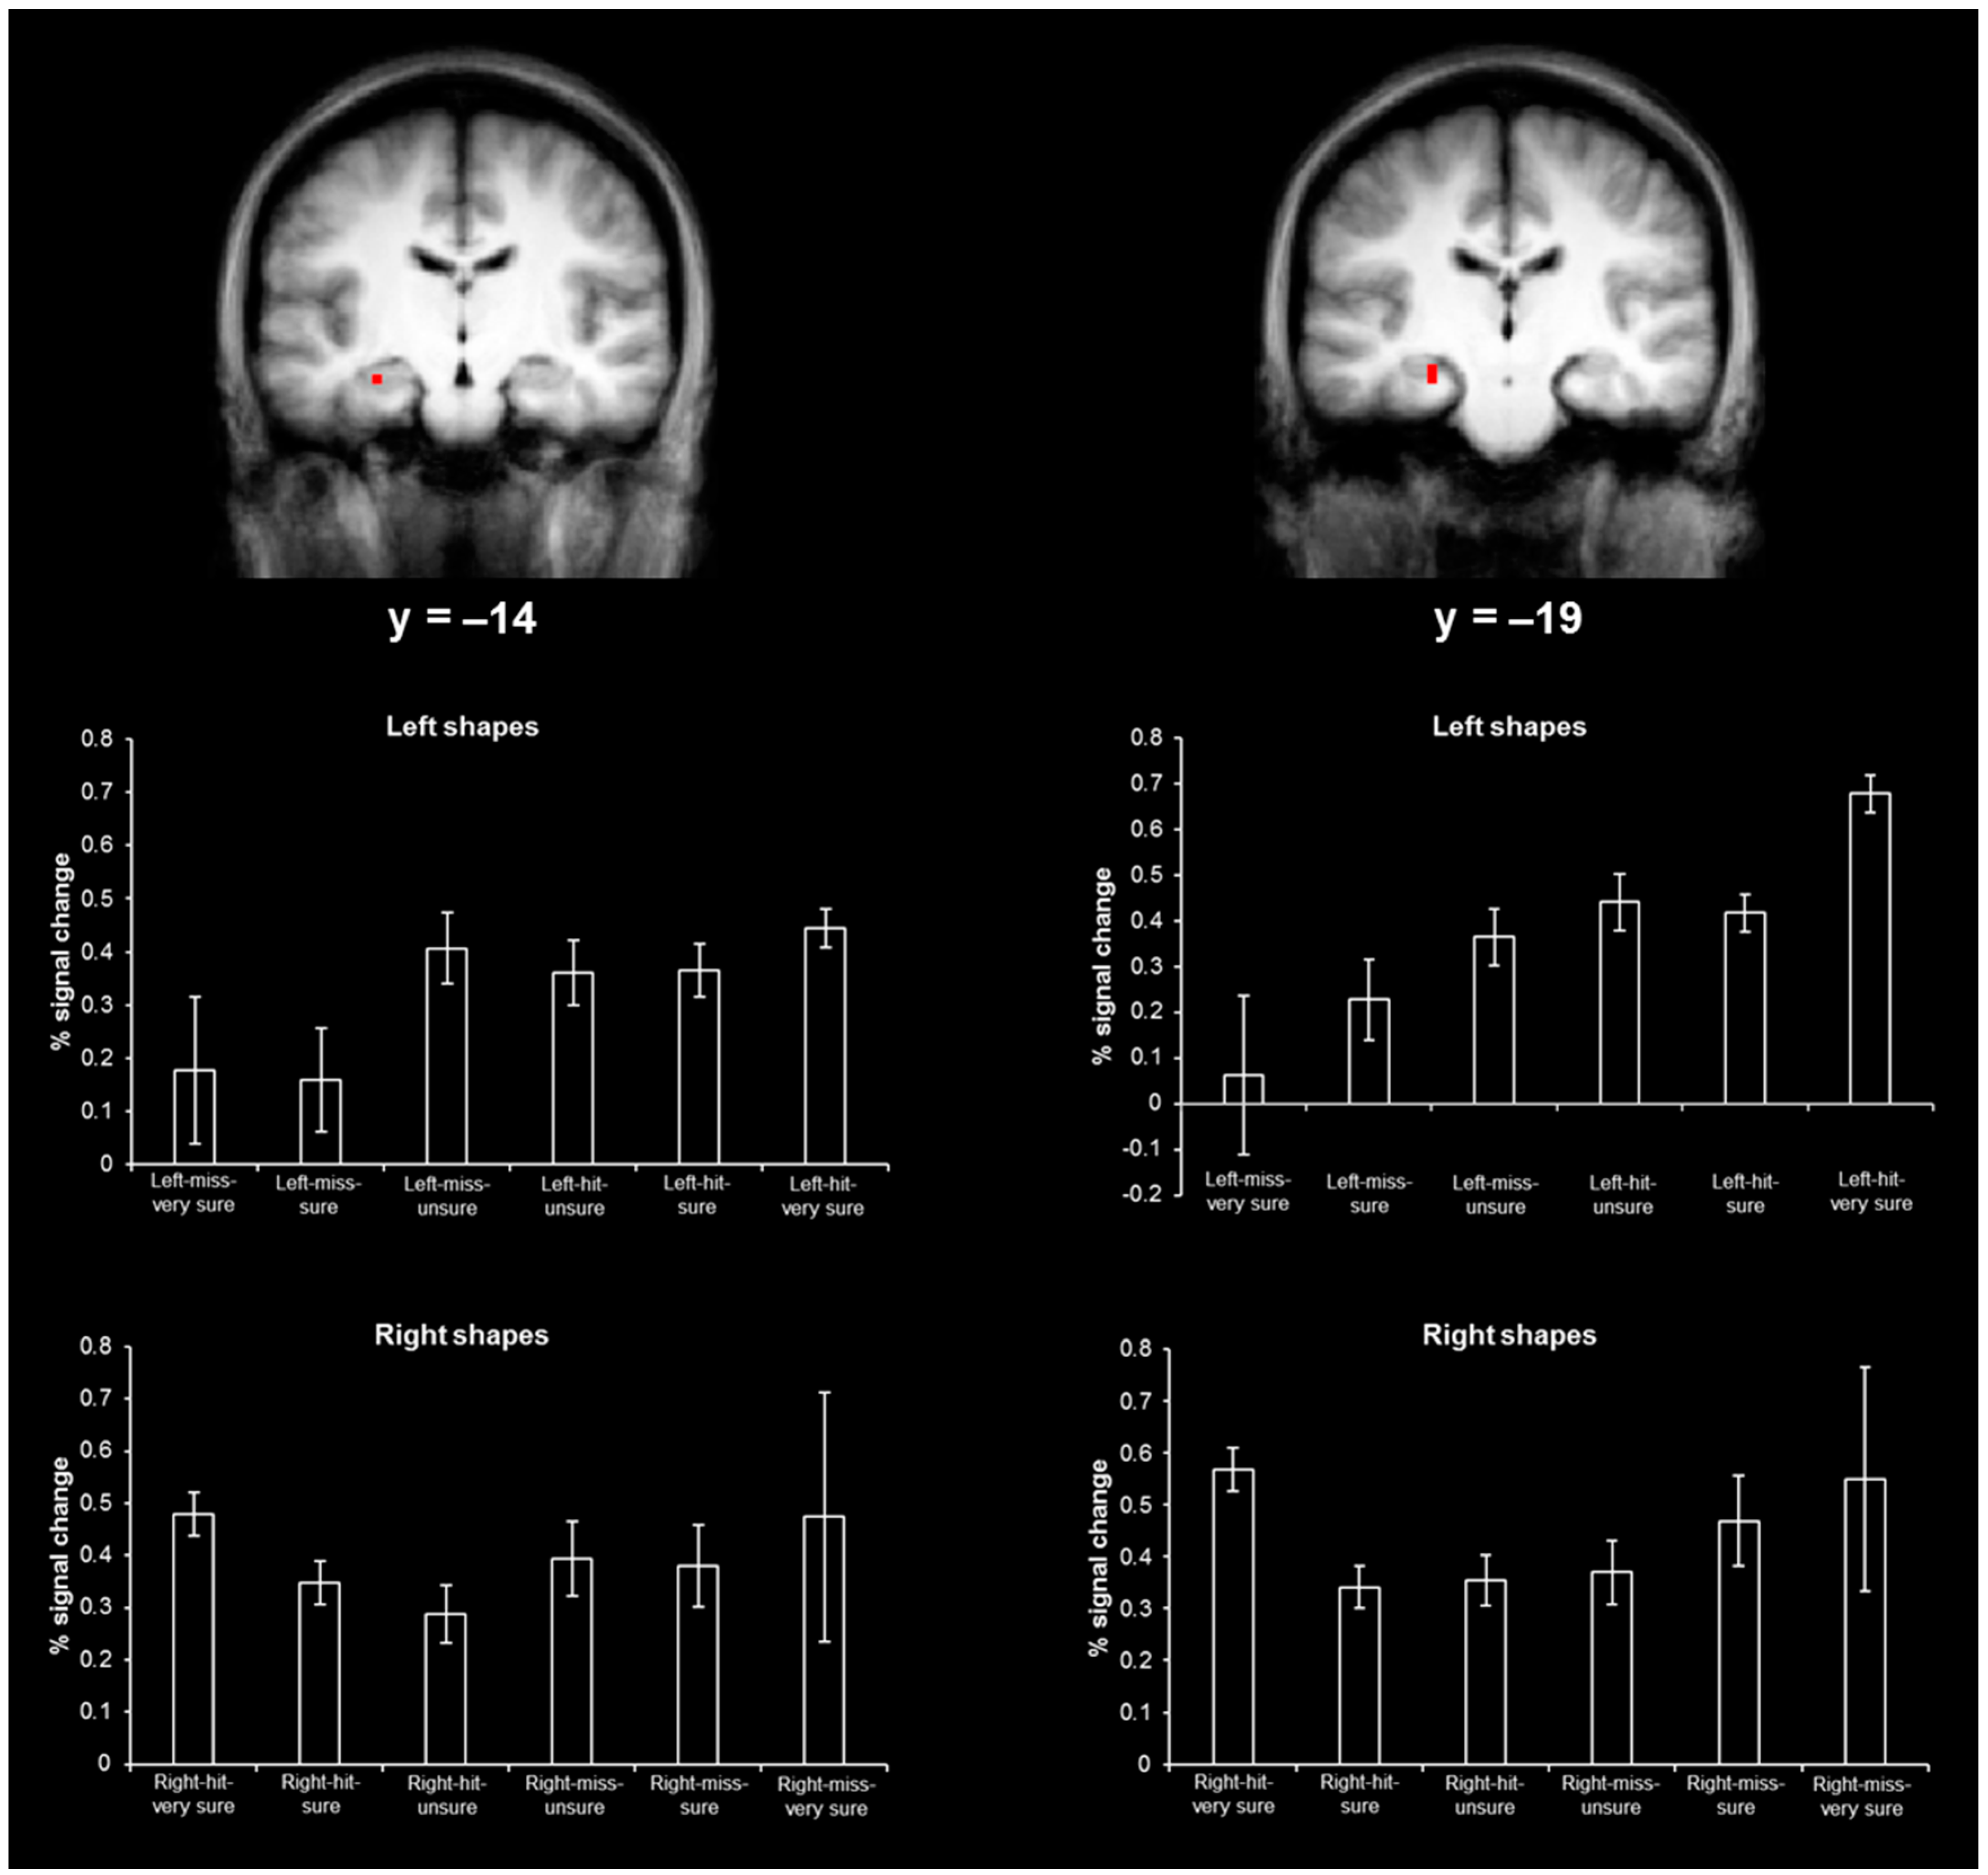

3.2. Hippocampal Results